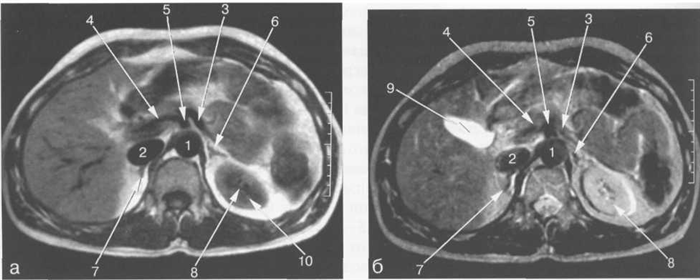

МРТ АНАТОМИЯ СЕЛЕЗЕНКИ

Неизмененная селезенка на Т1-ВИ имеет несколько большее время релаксации, чем паренхима печени, и характеризуется изоинтенсивным сигналом, более низким по сравнению с сигналом от печени. На Т2-ВИ селезенка имеет подчеркнуто высокую интенсивность сигнала и визуализируется как структура с более высокой интенсивностью сигнала по сравнению с печеночной паренхимой. Интенсивность сигнала селезенки соответствует параметрам кортикального слоя почек (см. рис. 11.9—11.12).

Рис. 11.24. MPT брюшной полости в аксиальной плоскости на уровне надпочечников.

а-Т1-ВИ;б-Т2-ВИ.

1 — аорта; 2 — нижняя полая вена; 3 — селезеночная артерия; 4 — общая печеночная артерия; 5 — чревный ствол; 6 — левый надпочечник; 7 — правый надпочечник; 8 — левая почка; 9 — желчный пузырь; 10 — Бертиниевы столбы левой почки.

Сосуды ворот селезенки хорошо видны во всех импульсных последовательностях (рис. 11.24). Селезеночная вена определяется как структура продолговатой формы, которая зачастую имеет горизонтальное расположение (см. рис. 11.12). Селезеночная вена используется в качестве ориентира для локализации хвоста и тела поджелудочной железы, которые располагаются кпереди от нее (см. рис. 11.12, 11.14). В области ворот внутриселезеночные сосуды видны как разветвляющиеся продолговатые структуры.